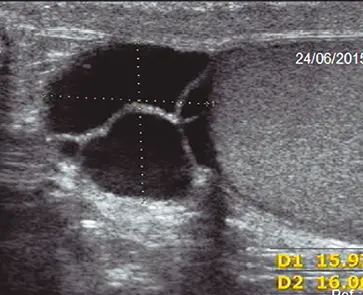

Fig: 8

Fig: 8– tabique menor de 3. 0 mm, vascularizado.